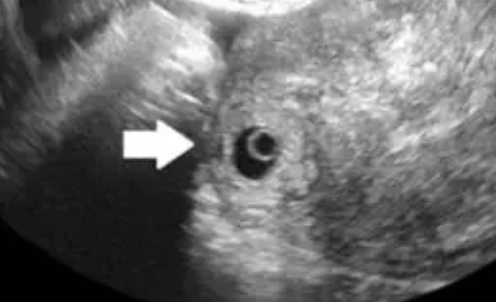

輸卵管間質部妊娠是指受精卵著床于輸卵管的間質段,是輸卵管妊娠的一種(圖 1),在所有異位妊娠中發生率為 2%~3%。輸卵管從外至內側分為四段:傘部、壺腹部、峽部、間質部。間質部段長約 1 - 2 cm,管腔內徑約 1 mm,橫穿宮壁上外側肌層,經輸卵管內口入子宮體腔宮角部。間質部段輸卵管管壁肌層分三層,血管化程度高,管壁周圍覆蓋著較厚的子宮角部肌層。間質部段緊鄰子宮、卵巢血管。子宮圓韌帶,起自子宮角部的前面,止于大陰唇前端。輸卵管間質部段位于子宮圓韌帶的外側。